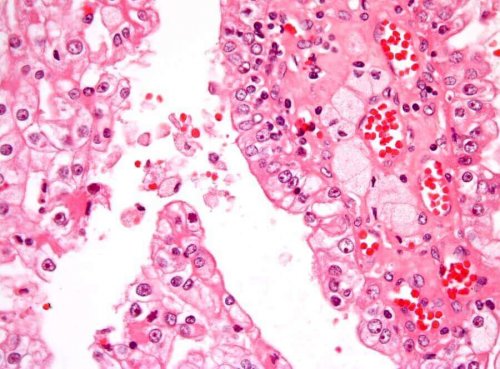

悪性細胞が体内で制御不能なほど増殖すると、がんが発生します。小児期の腎臓がんの最も一般的なタイプは、「ウィルムス腫瘍」または「腎芽腫」と呼ばれます。硬く、未熟な腎臓組織内で形成されます。